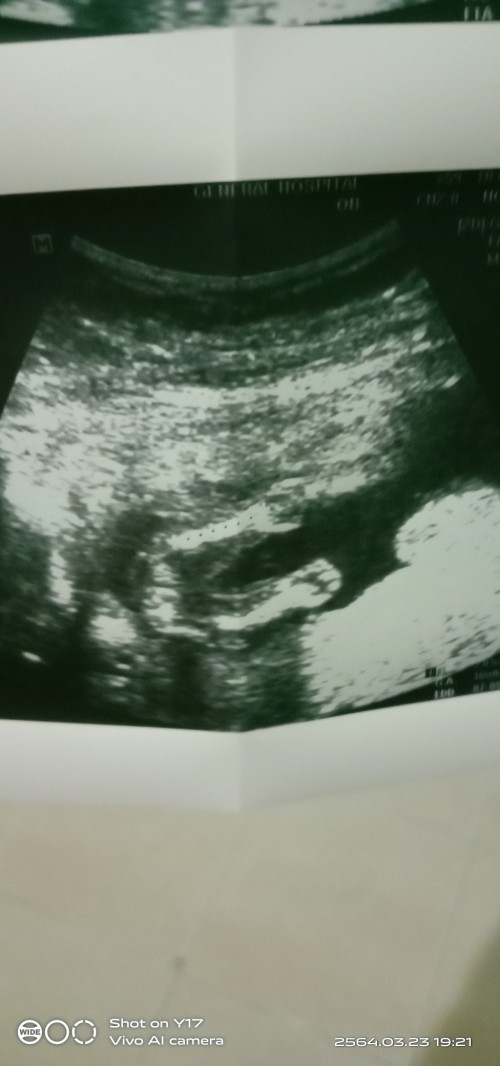

รูปตอน 16 วีคค่ะ ได้ลูกชายค่ะ

16w ค่ะ เห็นเพศแล้ว #ทีมลูกชายค่ะ

16 สัปดาห์ สาวน้อยจ้า

16w /หมอบอกลูกสาวจร้า❤

16วีคค่ะ ผู้ชาย